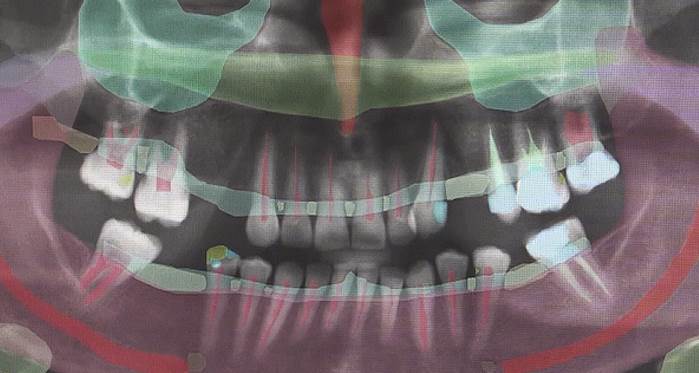

Ankara Üniversitesi Diş Hekimliği Fakültesi'nde "CranioCatch" adlı yapay zeka sistemiyle, hasta ağzındaki sorunların teşhisi ve dişe uygulanacak tedavi planlaması yapılarak, hekimin teşhis süresi kısaltılıyor, tedavi sonrasının görseliyle hastaya avantaj sağlanıyor.

"Yapay zekanın diş hekimliğinde iki çok önemli avantajı oluyor. Birincisi karar destek sistemi olarak kullanılabiliyor. Bir çürüğü atlayabileceğimiz hallerde, yapay zeka orada çürük olabileceği gibi size bir raporlama veriyor. İkinci avantajıysa görsel olarak hastaya da gösterebilme şansımız söz konusu oluyor."

Orhan, yapay zekayla hastanın, hangi dişinin tedavi edileceğinin ve hangi dişine ne uygulanacağının görselleştirildiğini kaydetti.

Hastanın çekilen filminin yapay zekaya aktarılmasından saniyeler sonra bütün teşhis ve patolojileri gösterdiğini belirten Orhan, şöyle konuştu:

"Filmin normal halini hastaya gösterdiğiniz zaman hastanın patolojileri algılayabilmesi mümkün olmayabiliyor. Ancak bunları 'Bu senin dişin, bu dişinin canlı kısmı, burada dolgun var, çürüğün var' diye gösterdiğimizde çok daha anlaşılıyor oluyor. Bu hekimlere de karar destek açısından önem arz ediyor. Çünkü burada bütün teşhisleri ve hastanın neyinin eksik olduğunu görebiliyorsunuz. Hatta tedavi planını da yapabiliyorsunuz. Yazılım, 'Hastanın tedavi planını bana ver' dediğinizde tedavi planını çıkartıyor. Hem hekimin teşhis süresini kısaltıyor hem de görsel olarak hastaya avantaj sağlıyor. Tedavi planlamasını hızlı bir karar destek sistemiyle hekimlere sunabiliyor."